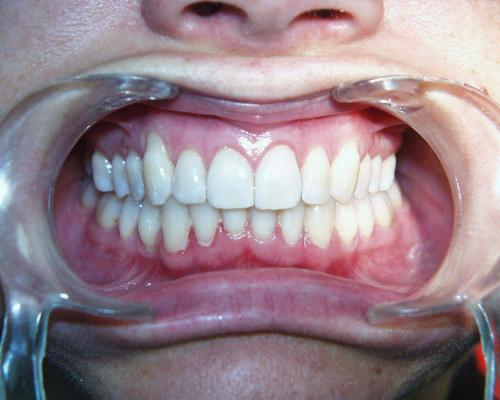

Nach der Behandlung

(Dauer der aktiven Behandlung: Im Oberkiefer 7 Monate, im Unterkiefer 1 Jahr, 4 Monate)